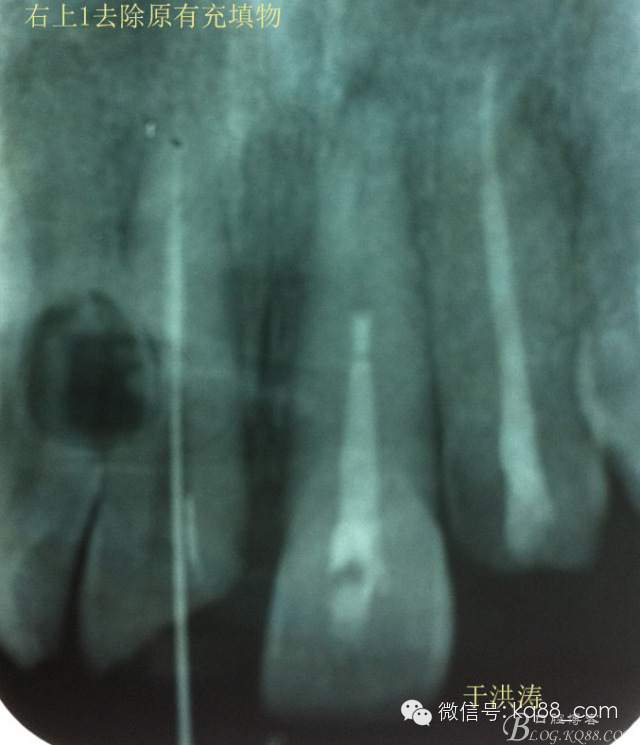

檢查:明顯可見22牙冠橫向斷裂至頸1/3處,近遠中與腭側斷裂至齦下??梢?/span>11牙冠斜向近中斷裂,近中與腭側均斷裂至齦下。21牙冠中1/3有裂痕。11 21 22松動(0),11 21叩(+),22叩(-),11 21 22探(-),11 21 22冷熱(-)。11 21 22唇側牙齦與粘膜和根尖相應部位未見明顯改變。11 22腭側牙齦增生性改變。11 21 22腭側粘膜和根尖相應部位未見改變。11 21 22舌側窩均有充填物。面部左右對稱無改變。余牙正常。(11,21,22牙冠顏色無改變)。 輔助檢查:X線片檢查11 22牙冠均有缺失。11 21 22 髓腔內均有充填物,11充填不到位, 21充填不實,22充填到位髓腔高密度影像。11 21 牙周膜有增寬,21根尖區(qū)有2mm左右低密度影像。未發(fā)現(xiàn)有牙根側穿或斷裂異物。 診斷:11,21慢性尖周炎,11,22殘冠。 治療計劃: 22無需治療。11 21 建議牙齒根管再治療。告知情況及費用。 1,11 21去除根充物。 2,11 21根管治療。 3,11 22纖維樁樹脂核修復。 4,高頻電刀去除11 22腭側牙齦組織到斷面。 5,11,21,22全瓷單冠修復牙齒。 治療過程:經(jīng)患者同意。H銼去除11 21原有充填物,未發(fā)現(xiàn)明顯滲出物,無異味。K銼疏通根管,VDW根測儀測量長度,11牙20mmWL,21牙20mmWL。S3鎳鈦器械預備根管。(全程1%次氯酸鈉沖洗EDTA溶解潤滑)試尖片顯示牙膠未到位,繼續(xù)向牙根尖各2mm進入預備。吸潮紙尖吸干根管,登士柏樹脂根充糊劑輸送至根尖部位,以測量數(shù)據(jù)用牙膠尖冷充側壓充填根管,3M玻璃離子封閉根管口。不可用患牙啃咬硬物,擇日冠修復。 輔助檢查:插針X線片顯示根管內充填物已經(jīng)取出。試尖片顯示牙膠尖未到位,繼續(xù)用K銼和機括向根尖預備。根充結束片顯示根充密實,無超充,無欠充。 醫(yī)囑:常規(guī)醫(yī)囑,不適隨診。 各步驟操作見下圖 于洪濤 2015.02.03 復 診 主訴:無疼痛,不適癥狀已經(jīng)消失。 檢查:11 21 充填物存在邊緣封閉完好,叩(-)松動(0)牙齦及周圍同初診。11 21 22無任何不適。 治療過程:由于患者自身原因即將兩個月來復診。拍X線片,去除11 22髓腔內部分牙膠,P鉆預備根管到達預定位置。粘結纖維樁,制作冠核。初預備11 21 22牙冠。高頻電刀按廠家要求功率和方法去除11 22腭側牙齦組織到達牙齒斷裂部位,調整檔位和功率繼續(xù)凝固和精修腭側組織,11 21 22排齦精修拋光。硅橡膠兩次法取模,可見模型完整肩臺清晰。制作臨時冠,科爾不含丁香油臨時冠粘結系統(tǒng)粘接。 模型送技師制作。預約義齒佩戴時間。(需術前牙齒比色) 輔助檢查:X線片顯示根尖低密度影像消失,牙周未見異常。X線片顯示纖維樁密合到位。 醫(yī)囑:不可用臨時牙肯咬硬物,不適隨診。 各步驟操作見下圖 于洪濤 2015.03.26 復 診 主訴:牙齒無癥狀,自感腭側術區(qū)舌舔粘膜不適。 檢查:臨時冠完整,無松動,邊緣緊密。牙齒無疼痛,唇側牙齦無明顯紅腫,腭側牙齦愈合良好,牙冠肩臺邊緣清晰。腭側牙齦術區(qū)中度觸及有少量滲血。 治療過程:義齒制作完成。去除臨時冠及粘結物。義齒試戴調整完全就位,無懸突,無縫隙。清洗義齒,氫氟酸處理義齒50秒(加強醫(yī)患防護),沖洗吹干,偶聯(lián)劑處理備用。基牙37%酸處理15秒,沖洗吹干,隔濕,排齦,涂第五代粘結劑。小蜜蜂雙固化樹脂水門汀激活攪拌注入義齒中,按順序就位,加壓力,牙線去除牙縫隙多余樹脂,涂阻氧劑,基牙唇腭側各光照固化3秒之后去除多余水門汀取出排齦線,繼續(xù)光照固化牙齒每個面20秒。精細查找去除多余水門汀。 醫(yī)囑:1,患牙咀嚼硬物加以注意。 2,常規(guī)醫(yī)囑,不適隨診,。 3,加強口腔衛(wèi)生意識。定期復診檢查。 各步驟操作見下圖 于洪濤 2015.04.07 回訪病例 主訴:咀嚼食物非常自如,無任何不適。 檢查:義齒牙體完整。無松動,無叩痛。唇側牙齦紅潤質韌無萎縮,腭側術區(qū)牙齦愈合良好,無炎癥改變。唇腭側根尖相應部組織無改變。余牙正常。 輔助檢查:X線片顯示牙根及周圍未見異常。未見骨萎縮。牙冠及頸部未見異常。 醫(yī)囑:定期檢查義齒,不適隨診。 各步驟操作見下圖 于洪濤2015.04.28